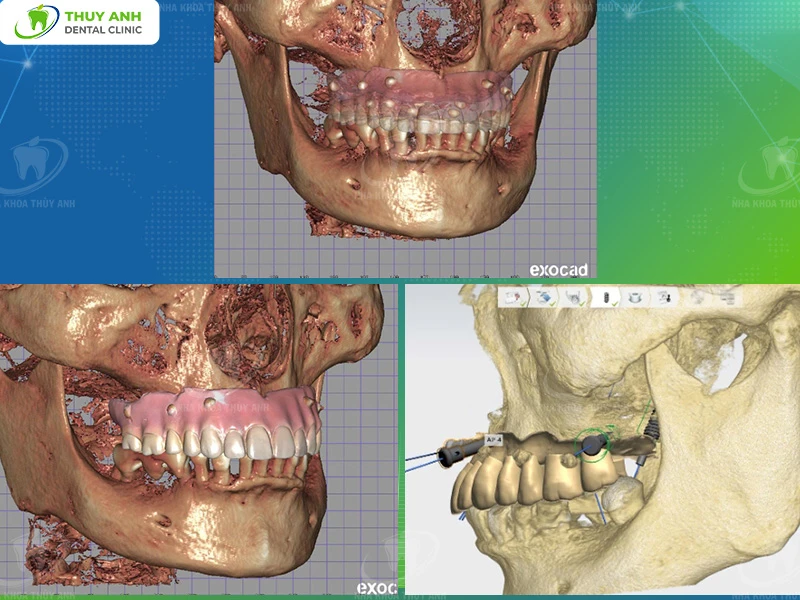

After collecting complete diagnostic data, all information was transferred into a digital treatment planning system.

This technology enables 3D analysis of the patient’s dental and jaw structure.

As a result, the doctor can:

- Accurately assess bone anatomy and related structures

- Determine optimal implant positions

- Simulate the final prosthetic outcome

For international patients, this step is particularly critical, as the entire treatment plan is established in detail before actual surgery.

This enhances both safety and predictability of the outcome.

Implant Surgery with Surgical Guide

Based on the digital treatment plan, a surgical guide was designed and fabricated.

This guide helps the doctor place implants precisely according to:

- Position

- Angle

- Depth